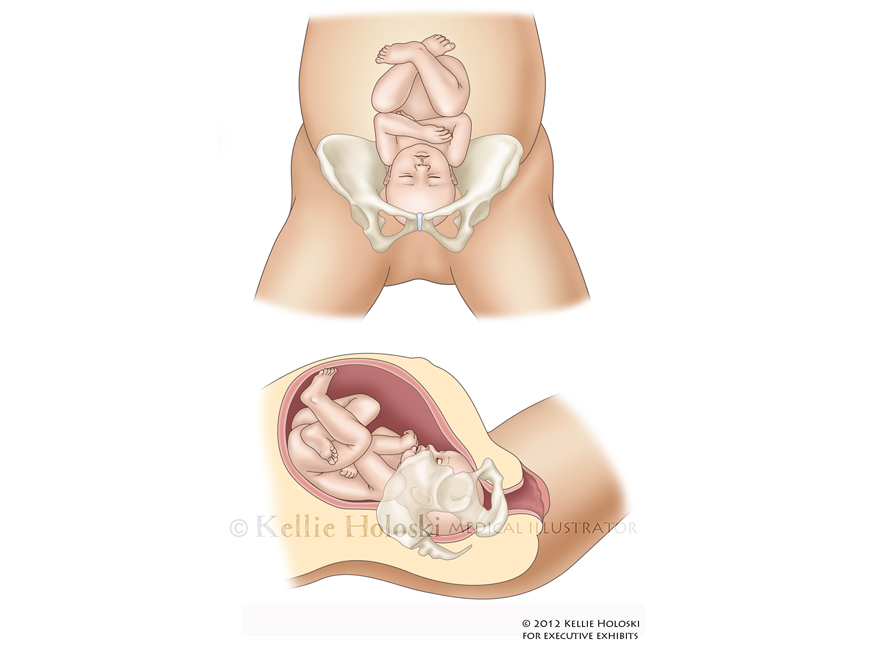

OP Birth,

Adobe Photoshop

Courtroom exhibit for Executive Exhibits;

©Kellie Holoski -